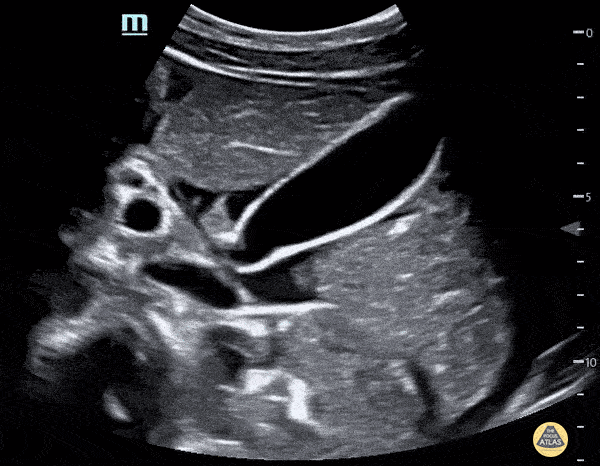

Bowel-GI - Ascites in Pregnancy

22 year old G3P2 female presented to the ER, 18 weeks pregnant, with central abdominal pain with radiation to her back. She was found to have large volume ascites of unknown etiology on US. She was admitted to the hospital and underwent paracentesis. A reminder to keep a broad differential for abdominal pain, even if the patient is pregnant. Michael Cannova, DO; Mara McMurray, DO